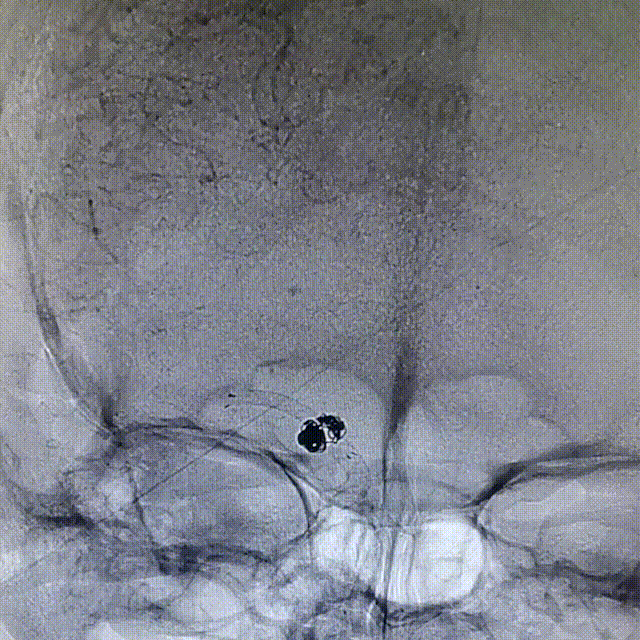

2周复查造影显示:3*3.2mm颈内末端动脉瘤一期采用Atlas支架辅助弹簧圈栓塞术后2周复发,动脉瘤体增大。

复查3D造影显示:3.5mm*4.4mm*3.2mm颈内末端动脉瘤一期采用Atlas支架辅助弹簧圈栓塞术后2周复发,动脉瘤体增大。

3D重建测量:

1)动脉瘤大小6.2*4.7mm

2)FD覆盖长23mm

3)远端血管2.4mm,近端血管3.5mm

动脉瘤的大小在短期内体积迅速增大,证实为血泡样动脉瘤。